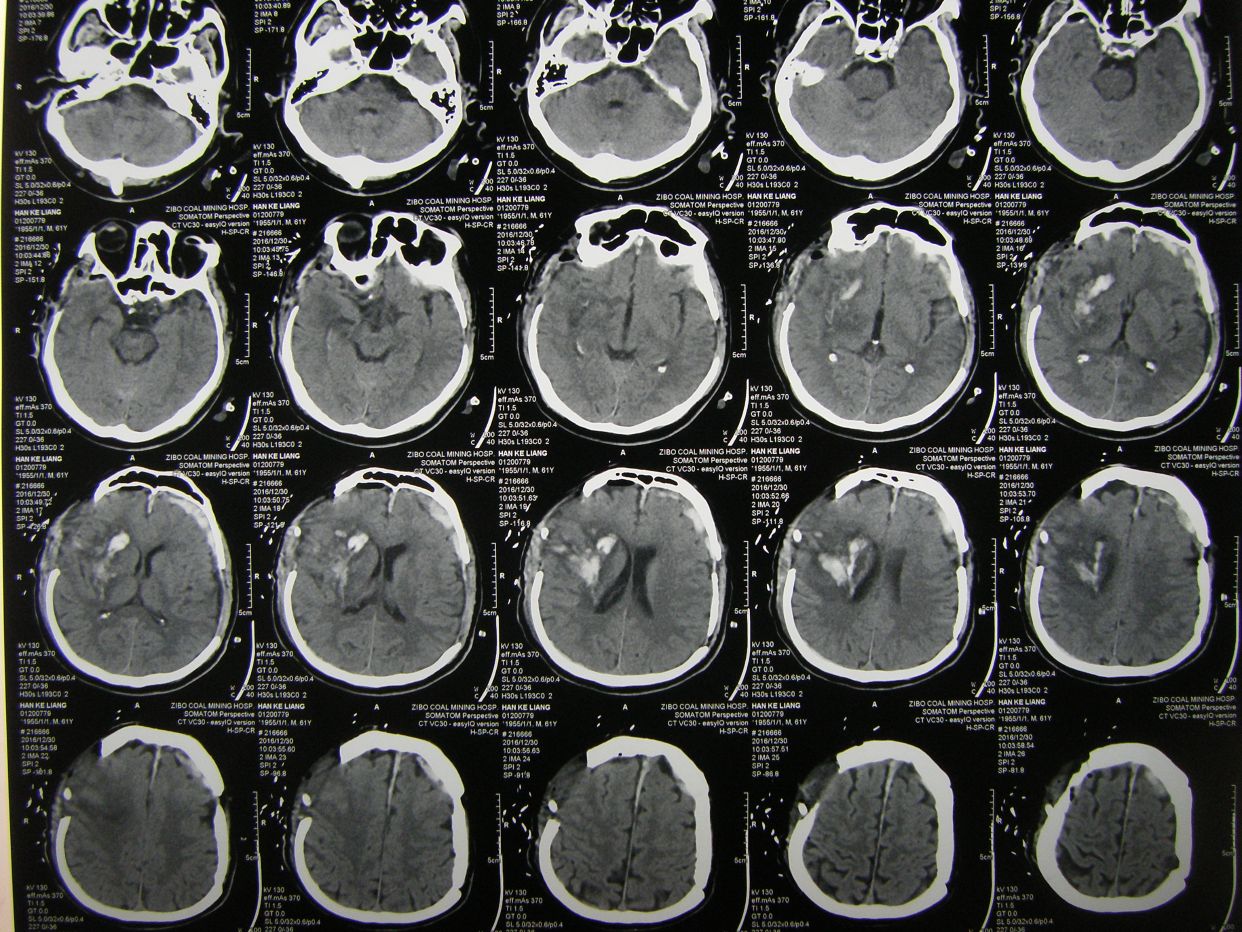

例2,男,63岁,被发现卧倒在地意识不清半小时入院。

CT示右额颞顶大量硬膜下血肿,右额颞叶脑挫裂伤,中线明显移位。急症全麻下开颅,血肿清除去骨瓣减压术,及气管切开术。

术后CT复查示,血肿清除彻底,中线居中,额颞叶水肿期。

术后8天,患者出现呼吸困难,氧饱和度下降,胸部CT示左侧肺野消失,考虑胃膈疝并肺不张肺感染。调整体位,拍背吸痰,应用呼吸机辅助呼吸等治疗。

术后3周CT复查,脑水肿消退,中线居中。

胸部CT复查,肺不张恢复,肺部阴影消退。患者恢复意识,遵嘱动作,呼吸良好,体温血象正常,出院康复。